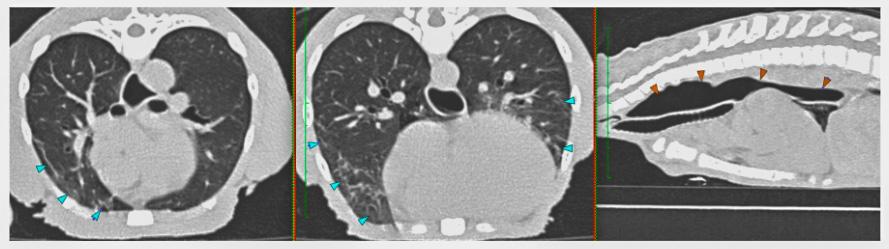

<div class="et_pb_text_inner"><p>From our perspective, being able to CT scan Smokey brought many advantages.</p>

<p><strong>Firstly</strong>, the procedure was very quick, which meant Smokey was only asleep for a short time — something that carries obvious benefits for his safety and recovery.</p></div>

<div class="et_pb_text_inner"><p><strong>Secondly</strong>, the scan provided us with an incredibly detailed and definitive diagnosis. We were able to rule out tumours, foreign bodies, and even ulcers. This allowed us to manage Smokey medically without the need for surgery. Operations in spider monkeys are always complex, and in Smokey’s case, there was an added concern: during the COVID lockdowns, he became stressed without visitors and pulled fur from his arm, so having a healing wound could have been a real temptation for him.</p></div>

<div class="et_pb_text_inner"><p><strong>Thirdly</strong>, the process caused minimal stress. Smokey was darted, anaesthetised quickly, and cared for using our ambulance’s anaesthetic facilities alongside the CT scanner. By the same afternoon, he was safely back in his pen and eating again.</p>

<p><strong>Finally</strong>, it was a real privilege for our team to be part of his care. Jess Nettleton, our Head Nurse, monitored the anaesthetic, while Deputy Head Nurse Robi McAffrey led the CT scan. We believe Smokey may now be the only red-faced spider monkey in the UK, which makes us fairly confident in saying we are among the very few teams to have ever performed a CT scan on a spider monkey!</p></div>